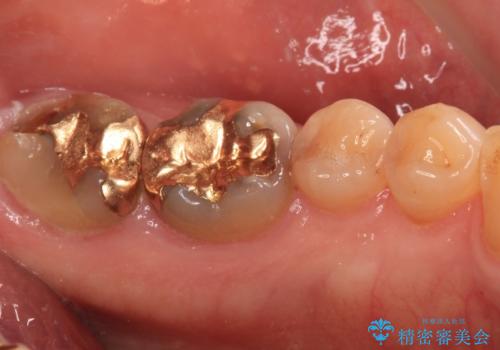

1番奥の歯はゴールドインレー周りがむし歯で欠けており、手前の歯はインレーの下にむし歯がある状態でした。

1番奥は歯肉に覆われている部分が大きいため、欠損部とむし歯の部分をゴールドインレーにて修復し、手前の歯はオールセラミッククラウンにて補綴治療を行うこととしました。

処置後はスッキリとした環境になりました。